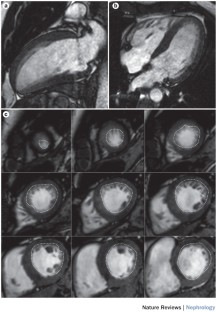

3D echocardiography is comparable to the 'gold standard' investigative tool of cardiac MRI for estimating left ventricular mass and volumes

Mor-Avi, V. et al. Fast measurement of left ventricular mass with real-time three-dimensional echocardiography: comparison with magnetic resonance imaging. Circulation 110, 1814–1818 (2004).

Krenning, B. J. et al. Three-dimensional echocardiographic analysis of left ventricular function during hemodialysis. Nephron Clin. Pract. 107, c43–c49 (2007).

Chiu, D. Y., Green, D., Abidin, N., Sinha, S. & Kalra, P. A. Echocardiography in hemodialysis patients: uses and challenges. Am. J. Kidney Dis. 64, 804–816 (2014).